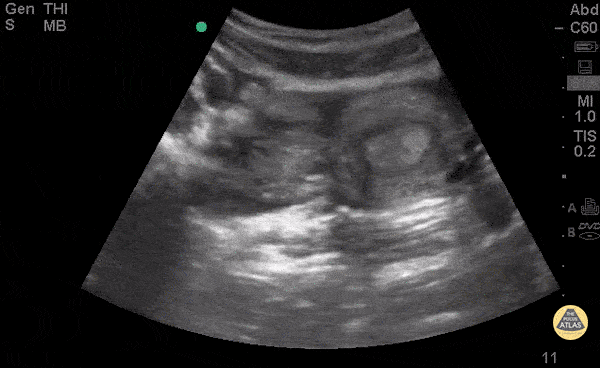

18yo F with 1 month history of abdominal pain presents with acute worsening of abdominal pain for 2 days. Exam revealed diffuse disproportionate pain to palpation of abdomen and right adnexal tenderness. POCUS demonstrates a hemorrhagic ovarian cyst defined by a cystic structure adjacent to the uterus with a well-defined wall and lacy/fishnet pattern within the structure. A hyper-acoustic shadowing can be seen distally along with free fluid surrounding the HOC. HOC can also be mistaken for a neoplastic ovarian mass. A distinguishing feature would be changes in fluid collection and changes in size of diameter of the cyst. Dr. Praneetha Chaganti, Dr. Andrew Aherne Kings County/SUNY Downstate Medical Center